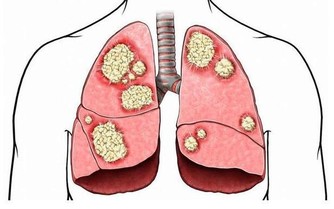

5.憋氣、口唇發紫:如果工作性質是久坐或長期站立,血液循環不好,

當病情發作時,除了疼痛外,

若還有憋氣、明顯的紫紺、口唇發紫、血氧下降等,就要高度懷疑可能是肺栓塞。

6.潛在病因:除了疼痛,還要警惕可能導致猝死的潛在病因。

比如,是否有易形成血栓的病史。

例如一位骨折病人,他 曾在一段時期內被限制運動,那麼他就容易發生靜脈血栓,

而靜脈血栓一旦掉下來,則可能發生肺梗死。